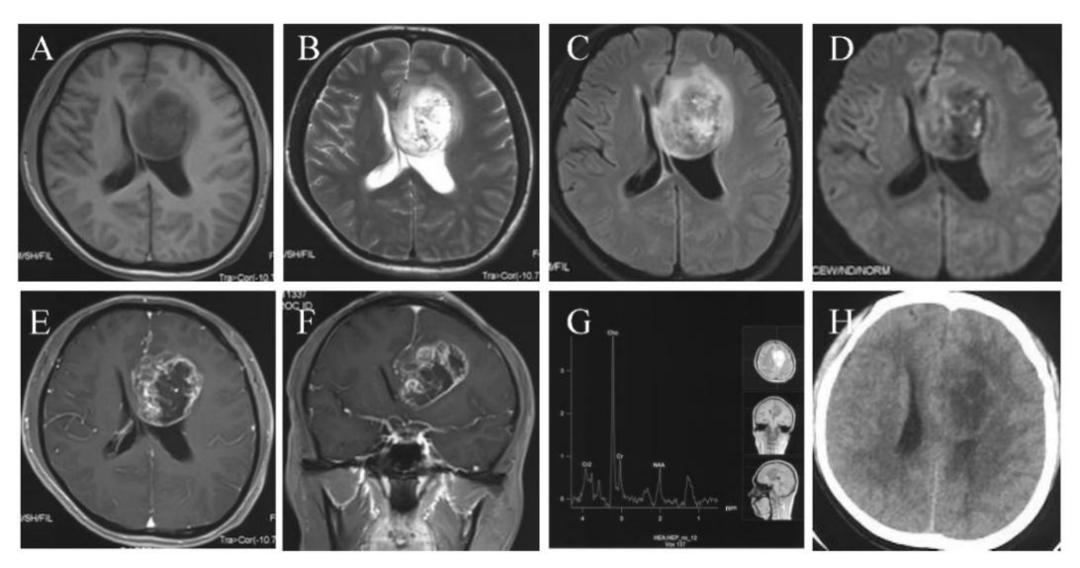

一名31岁男性患者,因间歇性头痛、恶心、呕吐3周后头痛逐渐加重、行走不稳就医。影像学检查提示:患者左额叶有5.4×5.2×5.0 cm环形强化灶,累及胼胝体、侧脑室前角及基底节区,伴瘤周水肿(图1)。此外,患者有癌症家族史,其母亲的两个姐妹都患有乳腺癌。基于影像学和临床判断,怀疑患者为胶质瘤,于2020年5月进行手术切除。

图1. 患者术前影像学